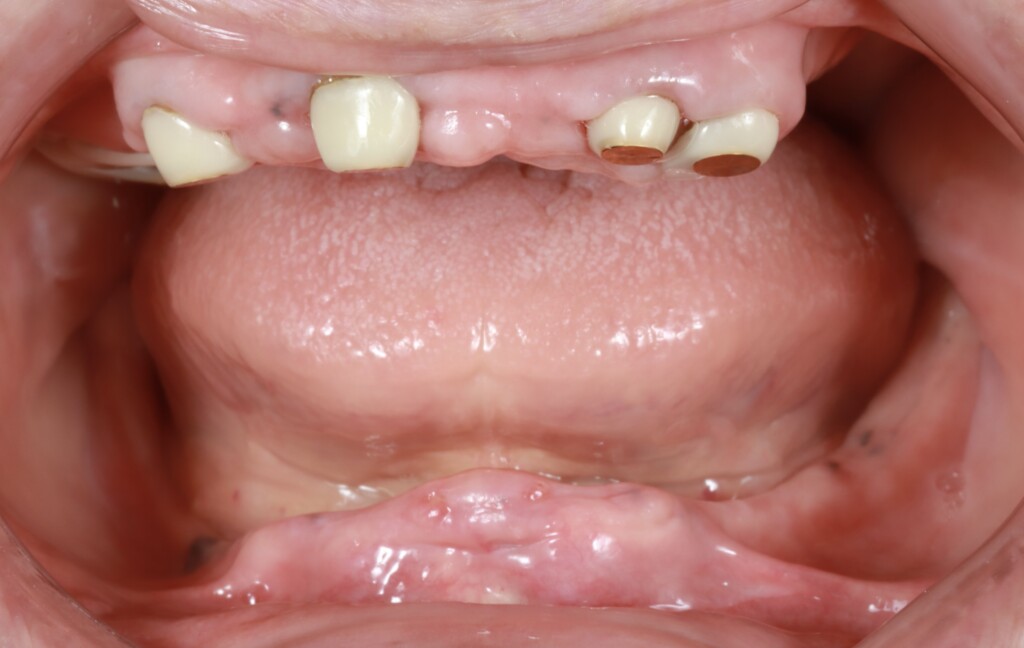

写真1:口腔内の正面観

*下顎は部分入れ歯を修理した総入れ歯が装着されている

写真3:下顎の歯ぐきの状態

写真4:上顎の状態

磁性アタッチメントが装着された状態(上顎)